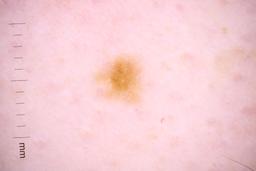

Description:

These are the images used in the paper: Analysis of the ISIC image datasets: Usage, benchmarks and recommendations

Paper Link: https://www.sciencedirect.com/science/article/pii/S1361841521003509

They have also been used by newer versions such as: Skin Lesion Classification Using Dermoscopic Images and Clinical Metadata: Insights from Multimodal Models